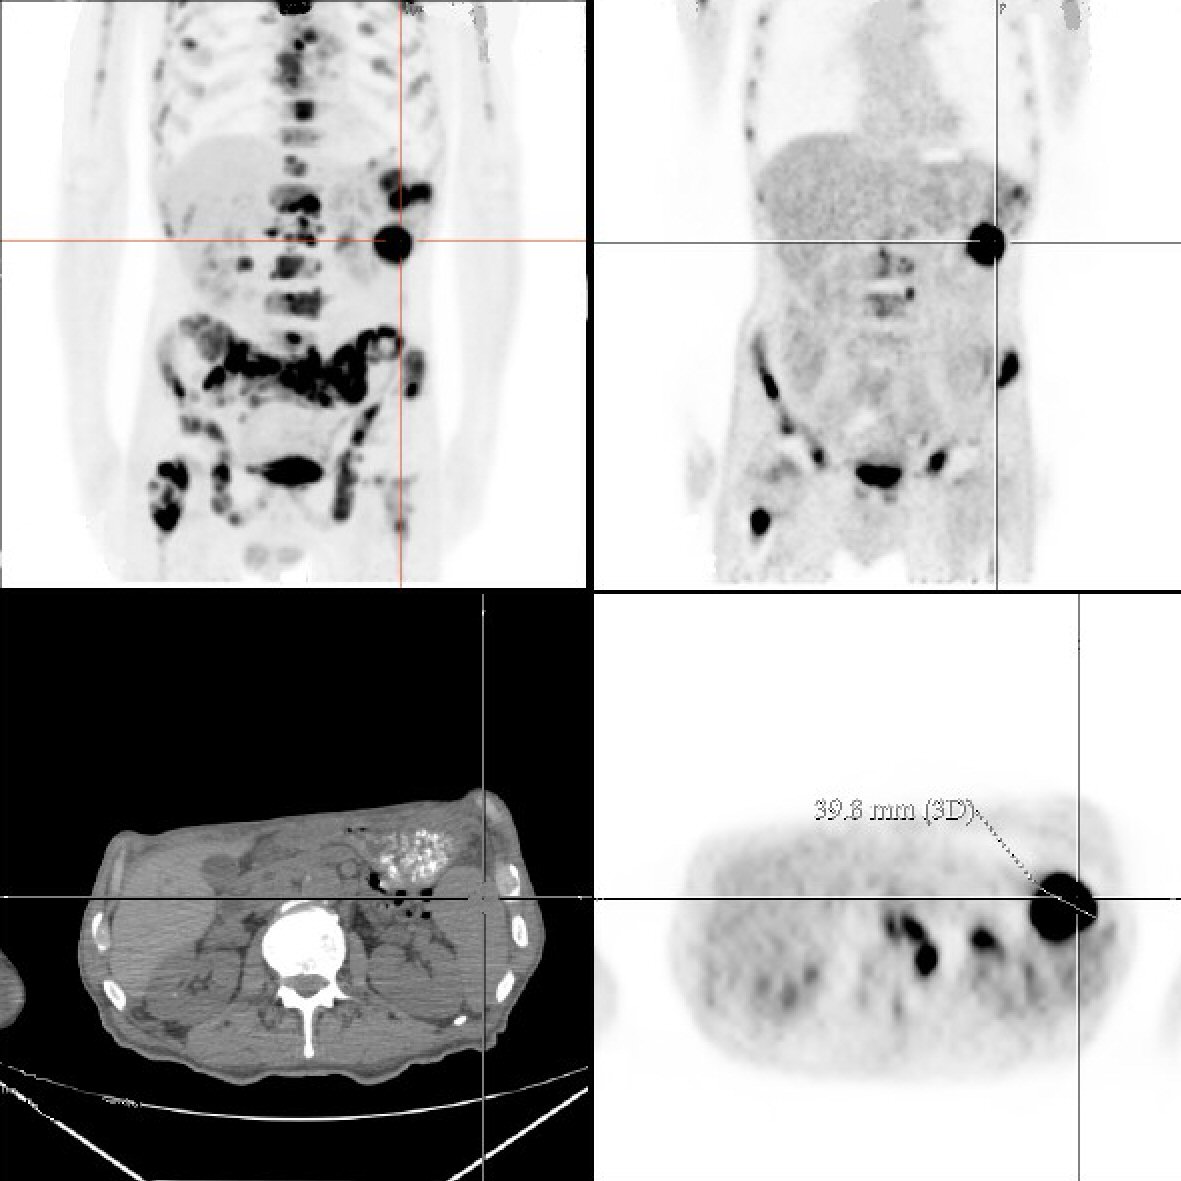

Throughout his hospital stay the patient remained on intravenous maintenance normal saline at 150 mL/h, and his creatinine improved to 1.68 prior to discharge. In addition, patient received intravenous calcitonin, one dose of intravenous pamidronate and furosemide, and zoledronic acid for symptomatic hypercalcemia which significantly improved his calcium to 10.9 at its lowest. The patient was discharged in a stable condition with close follow-up. A following outpatient positron emission tomography/computed tomography (PET/CT) scan showed extensive skeletal metastatic disease with fluorodeoxyglucose (FDG) uptake involving all bones, 5-cm mediastinal mass and diffuse splenic disease with 3.98-cm mass, an atypical presentation of lymphoma (Fig. 2). The patient’s international prognostic index (IPI) was 4 which indicated high risk for shorter overall survival, specifically 26% chance 5-year survival according to the International Peripheral T-cell Lymphoma Project [12]. The patient consistently followed up as an outpatient with medical oncology and completed four cycles of hyperfractionated cyclophosphamide, vincristine, doxorubicin and dexamethasone (hyper-CVAD) chemotherapy without complications. After 8 months of initial presentation, repeat PET/CT showed complete remission of his lymphoma with improvement of labs. The patient remained in complete remission for over 1 year since the end of treatment. At his most recent office visit, patient was asymptomatic with positive weight gain and normal appetite.

![]() Click for large image | Figure 2. Torso positron emission tomography/computed tomography scan demonstrates diffuse fluorodeoxyglucose (FDG) uptake and a 3.98-cm splenic mass. |